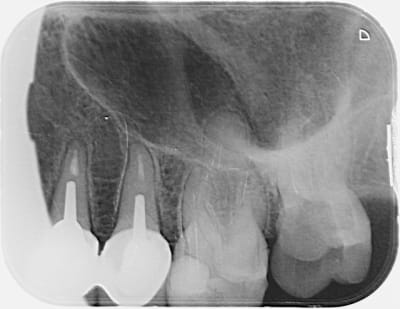

Première fracture d instrument!

SX (protaper) fracturé dans le 1/3 coronaire de la racine mésiale de la 27, après reconstitution de l'instrument il doit y avoir 3 mm.

J'ai essayé de passer des limes en ouvrant bien aux ultrasons avant mais pas de résultat

Je bute sans cesse sur l'instrument